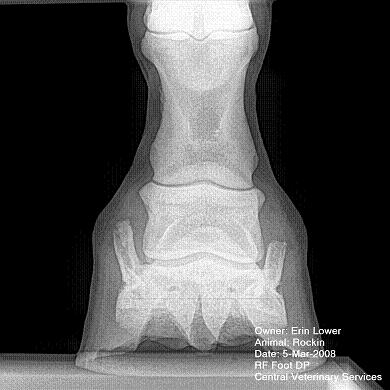

So, Rockin's x-rays were sent to a radiologist and he confirmed "normal" changes in the navicular bones for a horse her age, but slightly more significant ones in the right (sore) foot.

She also has sidebone in both fronts, but apparently that isn't causing any discomfort.

Finally, she has a "small chronic exostosis on the lateral aspect of the proximal phalanx" which, according to the radiologist, shouldn't be causing discomfort but I have read that these can be mild-to-moderately painful... I wouldn't mind another opinion on that.

I will attach as many images as possible from her x-rays (there are many different views). I don't have any pics of the feet as someone deleted them from my camera before I could download them. I'll try to take pics next time she is trimmed. Please, anyone with knowledge of hooves, give any opinions that you might have (especially Dr. O!)

I cannot rule out lesions based on these images but I will take your radiologist's word that he does not see significant lesions. The exostosis on the RF would be above the level of a well conducted PDN which I believed blocked the lameness before?

DrO